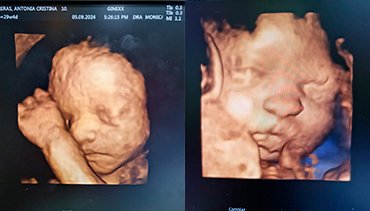

Una ecografía en 3D o tridimensional es una técnica de diagnóstico por imagen que utiliza ondas sonoras para crear imágenes detalladas del interior del cuerpo, especialmente de órganos o estructuras en desarrollo, como un feto en el embarazo. A diferencia de la ecografía tradicional en 2D, la ecografía en 3D proporciona una visualización más realista y detallada, permitiendo ver la forma, tamaño y posición de los órganos o el bebé desde diferentes ángulos. Esta tecnología es comúnmente utilizada en obstetricia, pero también puede aplicarse en otras áreas médicas.

La ecografía 3D nos permite obtener una imagen tridimensional del útero, ovarios, trompas de falopio y vagina. Su importancia radica en la aportación del tercer plano, lo que supone un cambio sustancial en el estudio de los órganos de la pelvis femenina, ya que es posible observar y analizar volumétricamente tales órganos (en tiempo real si se trata de 4D).

Este examen permite el estudio de malformaciones uterinas, patologías de la cavidad del útero (pólipos, miomas, tabiques, etc), quistes o tumoraciones en los ovarios.

⚛ Ecografías 2D-3D